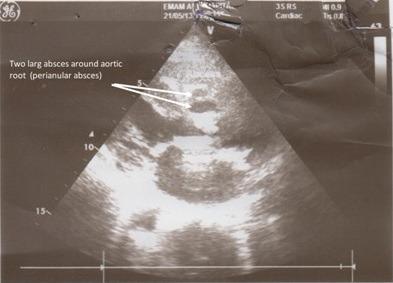

A rare case of prosthetic aortic valve endocarditis complicated with multiple fistula to peri aortic structure.

Multiple aorto-cardiac cavity communications is very rare but important complication of prosthetic aortic valve endocarditis. The case below illustrates multiple aorto-cardiac cavity fistula formation following prostethic aortic valve endocarditis presented with slowly progressive symptoms of heart failure. A brief review of surgical reconstruction and the existing literature are presented, including emphasis on pre and intra operative echocardiographic diagnosis and treatment.

多发性主动脉-心腔交通是人工主动脉瓣心内膜炎非常罕见但重要的并发症。以下病例说明了人工主动脉瓣心内膜炎后多发性主动脉-心腔瘘的形成,表现为心力衰竭的缓慢进展症状。本文简要回顾了手术重建及现有文献,重点强调术前和术中超声心动图诊断及治疗。